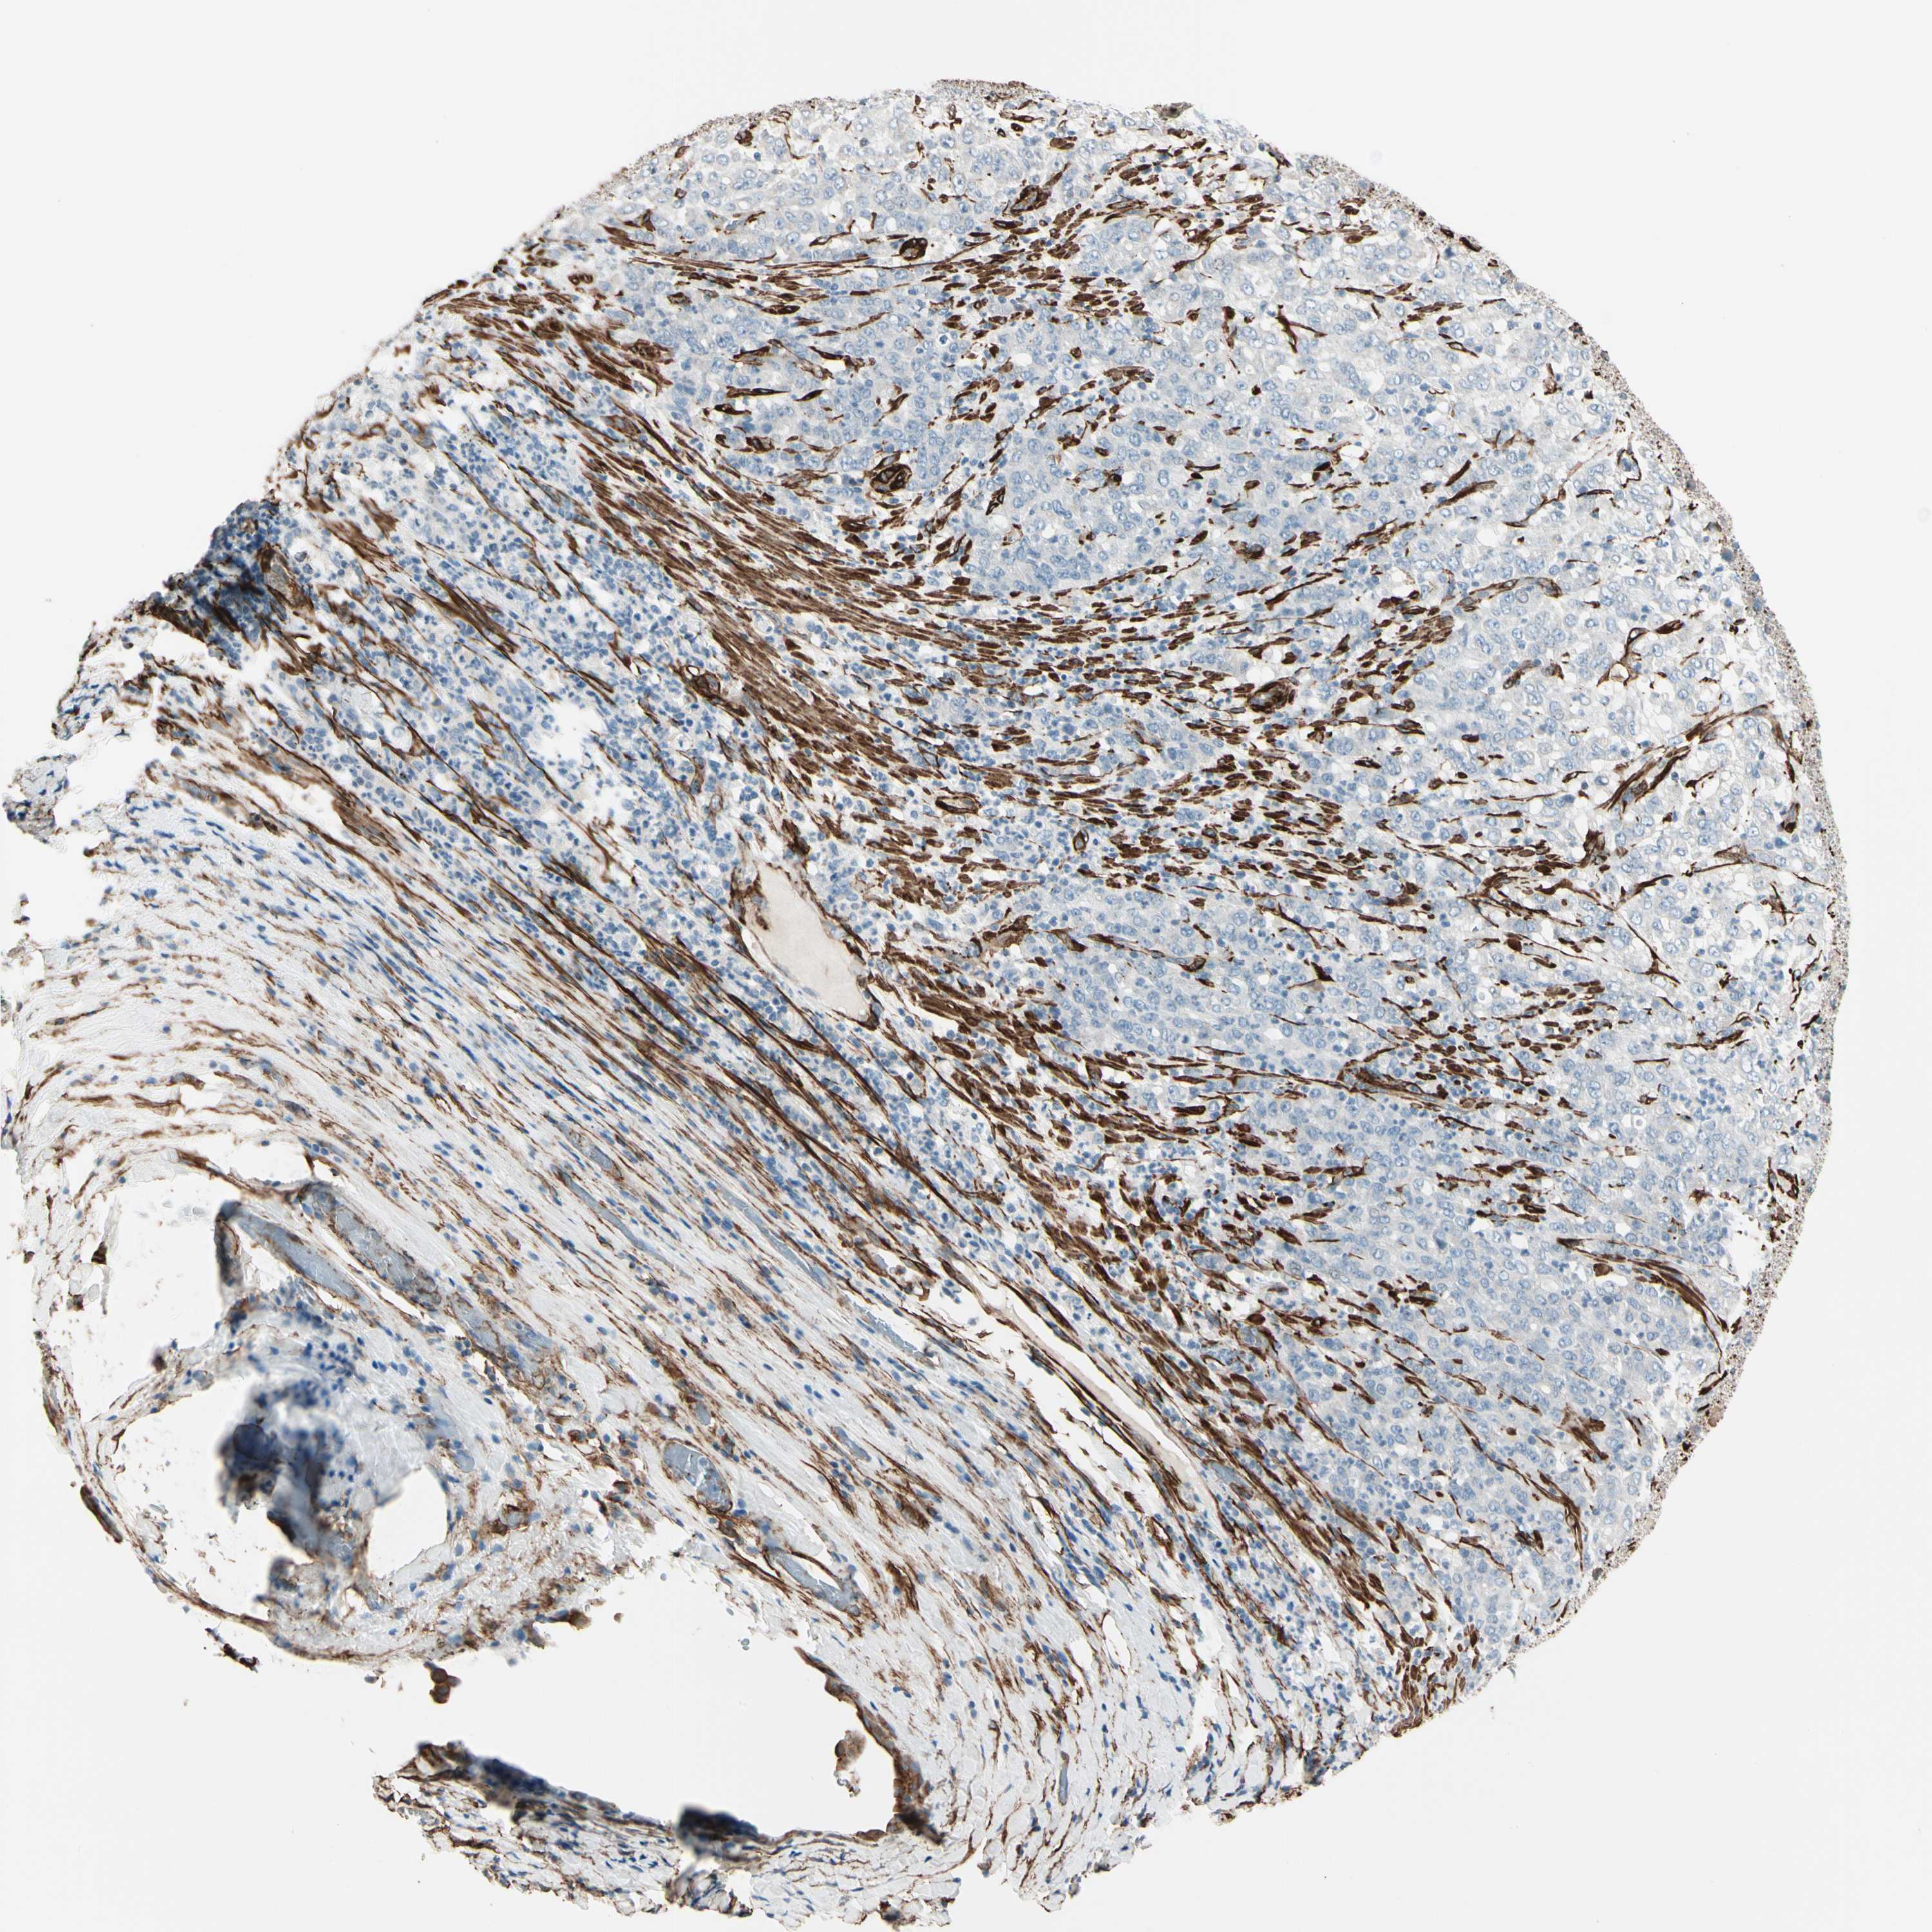

STOMACH CANCER - Protein expressioni

A mouse-over function shows sample information and annotation data. Click on an image to view it in a full screen mode. Samples can be filtered based on level of antibody staining by selecting one or several of the following categories: high, medium, low and not detected. The assay and annotation is described here.

Note that samples used for immunohistochemistry by the Human Protein Atlas do not correspond to samples in the TCGA dataset.

Antibody stainingi

Antibody staining in the annotated cell types in the current human tissue is reported as not detected, low, medium, or high, based on conventional immunohistochemistry profiling in selected tissues. This score is based on the combination of the staining intensity and fraction of stained cells.

Each image is clickable and will lead to virtual microscopy that enables deeper exploration of all samples and also displays staining intensity scores, fraction scores and subcellular localization as well as patient and tissue information for each sample.

Antibody HPA008066

Antibody HPA017330

Antibody CAB000006

Staining

High

Medium

Low

Not detected

Intensity

Strong

Moderate

Weak

Negative

Quantity

>75%

75%-25%

<25%

None

Location

Nuclear

Cytoplasmic/membranous

Cytoplasmic/membranous,nuclear

Adenocarcinoma, NOS